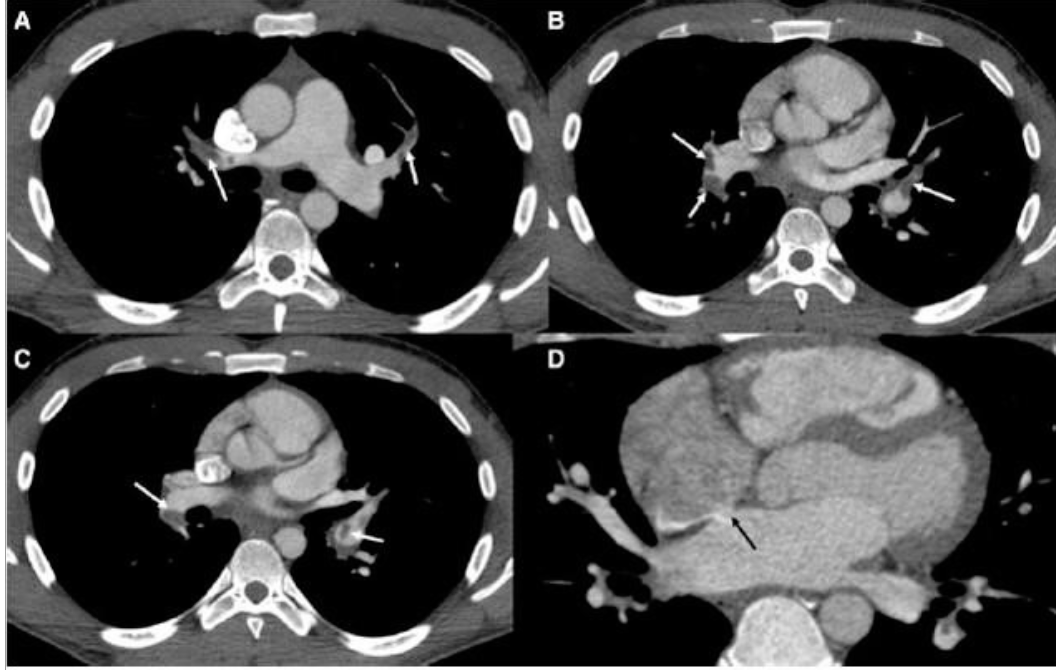

22세 남자가 호흡곤란으로 입원하였다. 환자는 3년 전 항인지질항체증후군(antiphospholipid syndrome)을 진단 받았다. 한 달 전 고속버스를 타고 장시간 여행한 후부터 오른쪽 장딴지에 통증이 있었으며, 10일 전부터 시작된 호흡곤란이 내원 하루 전부터 급격히 악화되었다. 흉부 컴퓨터단층촬영(Computed tomography, CT)에서 양측 폐동맥 색전증(사진 A의 A, B, C, 흰색 화살표)과 심장의 심방중격결손(atrial septal defect)이 발견되었다(사진 A의 D, 검은색 화살표). 입원 4일째 갑자기 발생한 오른쪽 상지와 하지의 근력 약화로 시행한 뇌 CT 에서 왼쪽 중대뇌동맥 주변에서 뇌경색 소견이 관찰되었다(사진 B의 흰색 화살표). 이 환자에게서 뇌경색이 발생한 이유를 가장 잘 설명한 용어는?

(사진 B)